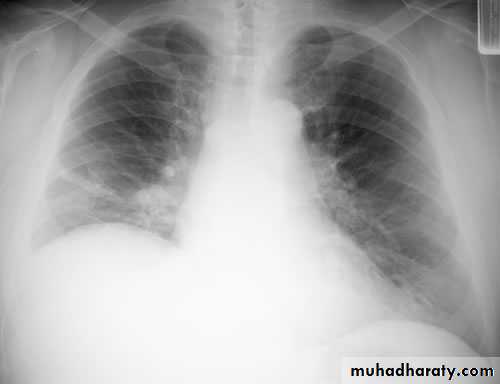

The main aims of investigations are to confirm the diagnosis, establish the histological cell type and define the extent of the disease.1-CXR: common radiological features of bronchial carcinoma;

Unilateral hilar enlargement.

Peripheral pulmonary opacity.

Lung, lobe or segmental collapse.

Pleural effusion.

Broadening of mediastinum, enlarged cardiac shadow, elevation of a hemidiaphragm.

Rib destruction.